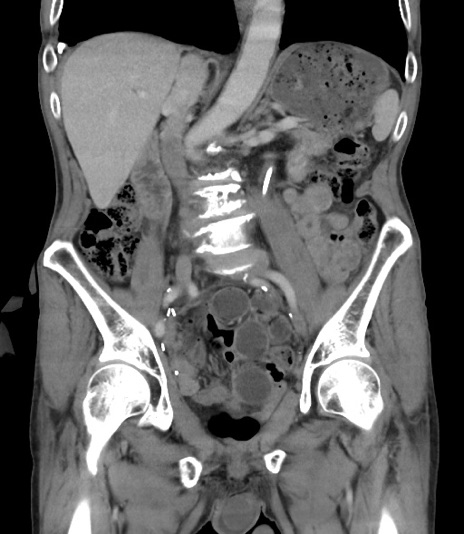

症例3(冠状断像)

【症例】 70歳代男性

【主訴】右鼠径部腫瘤、疼痛

【現病歴】本日朝より上記主訴あり、受診。

【既往歴】膀胱癌にて膀胱全摘、両側尿管皮膚瘻

【データ】WBC 5600、CRP 0.56